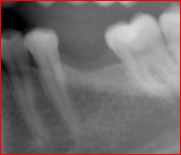

Replacement of failing lower back teeth

Immediate implant molar replacement involves placing a dental implant directly after tooth extraction in a single, minimally invasive procedure. This technique reduces healing time and preserves jawbone structure. It’s ideal for patients seeking swift treatment without extensive surgical intervention, enhancing overall dental care efficiency.

POSTERIOR IMPLANT

This patient came to see Dr. Andrews in our Boston Dental Practice with the desire to replace her missing lower left molar (#19). Since the extraction was done more than a year prior to the visit, more than 50% of the bone volume was lost. Being the second biggest tooth in the mouth, a lower molar requires a strong foundation to be built on.

Studies confirmed, that for long-term success, an implant diameter for such case should be no less than 5 mm. With only 3 mm width of the bone available here, no implant can be placed without a bone graft. The classic (old) treatment planning dictates the two-stage approach. The bone graft (ridge augmentation) is done first. After 4-5 months, when the bony ridge is wide enough (10-12 mm), an implant is placed. Then another 5-6 months are required for the implant to integrate with the bone. Add another month to make a crown. Thus, the total treatment time is 10-12 months.

Using modern, advanced surgical techniques, combined with PRF protocol, Dr. Andrews was able to combine bone graft with the simultaneous implant placement. He augmented the bone ridge wide enough to place 7 mm implant diameter. That is 200% more implant-to-bone surface area compared to a 5 mm one. Such a strong foundation should be able to support the implant crown for the entire patient’s life. This case took Dr. Andrews 5 months to complete, with only one surgery.